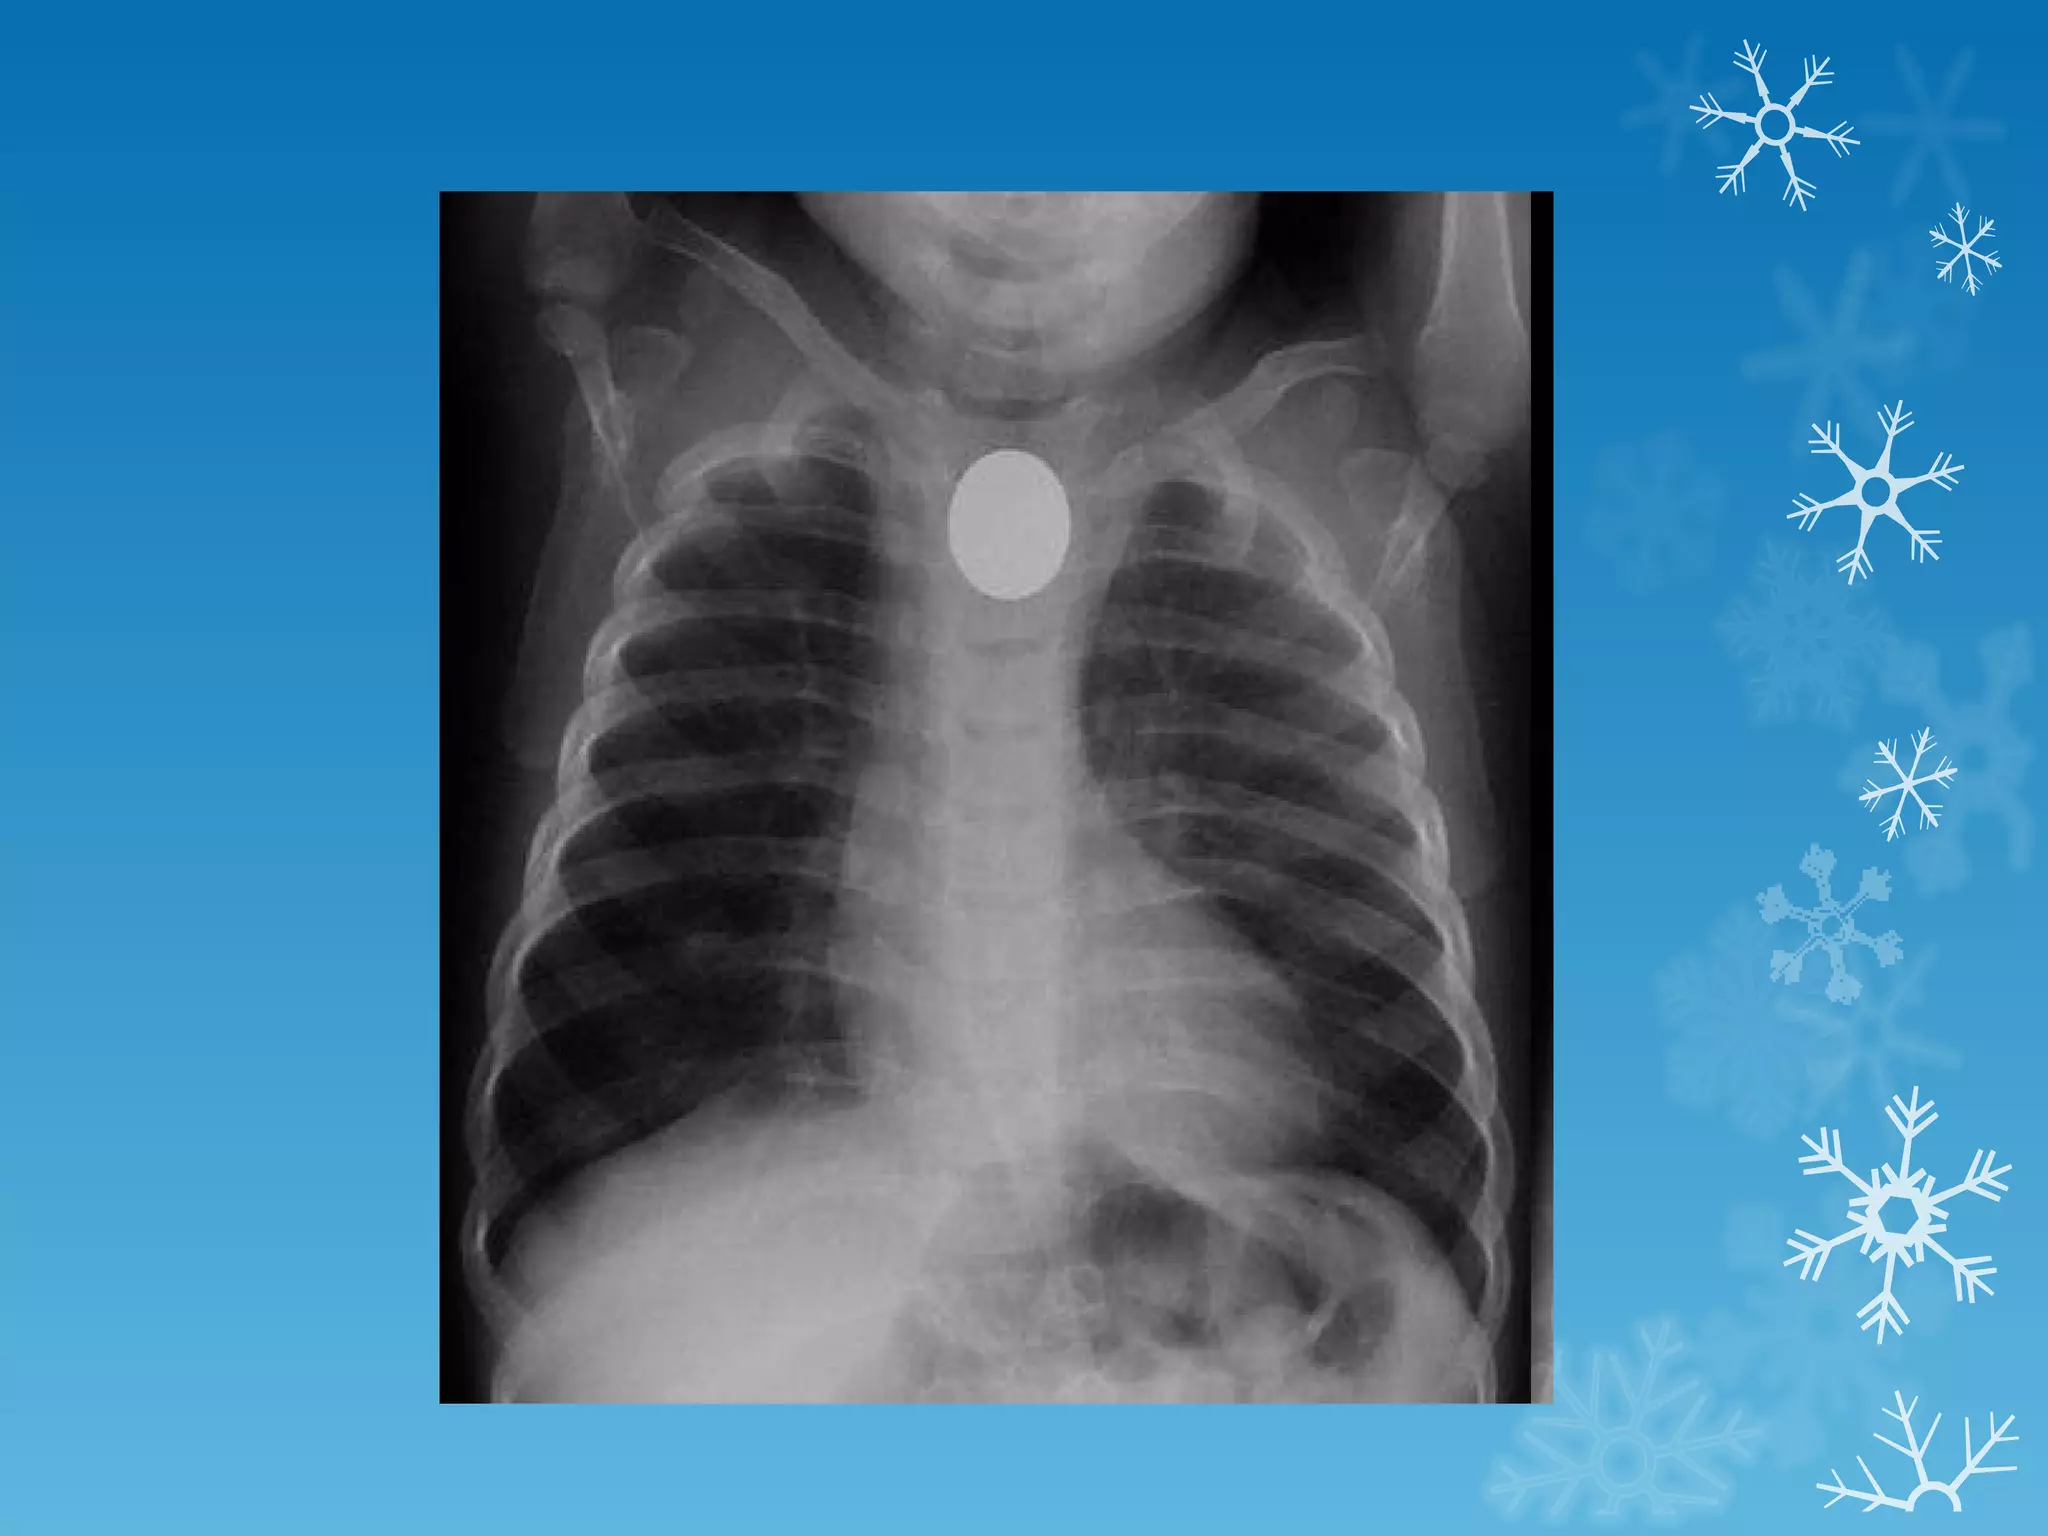

This document discusses chest x-ray interpretation and provides guidance on evaluating x-rays. It explains that tissue density determines how an x-ray beam penetrates, with denser tissues appearing whiter and less dense tissues appearing blacker. It also outlines different chest x-ray views and factors to consider like patient orientation, age, gender, and rotation. Abnormalities are described as appearing too white, too black, too large, or in the wrong place. The document stresses a systematic approach of identifying, localizing, describing lesions, and providing differential diagnoses.